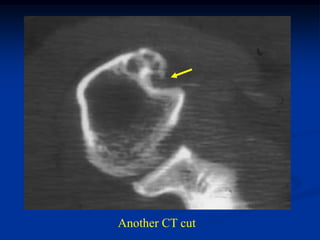

Case #595

46 year female with periosteal chondroma humerus

CT scan

Another CT cut

Coronal T-1 MRI

Coronal T-2 MRI

Photomic